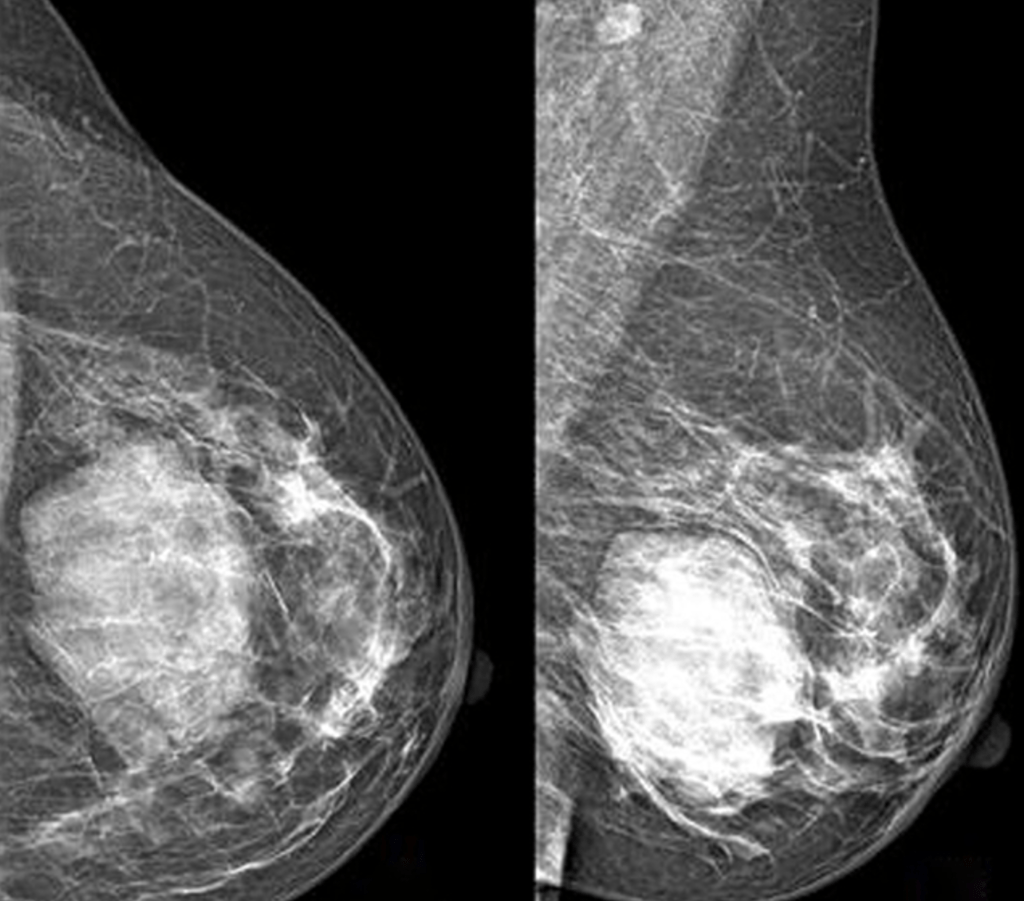

Image: Mammography performed with craniocaudal (A) and mediolateral oblique (B) incidences of the left breast shows a huge well-defined mass located between the inner and the outer inferior quadrants, with no suspicious features

- On mammography:

- The most common appearance described is:

- A well-defined, uncalcified mass, with regular borders

- Spiculated borders, suspicious borders, and architectural distortion can also be seen:

- But are uncommon